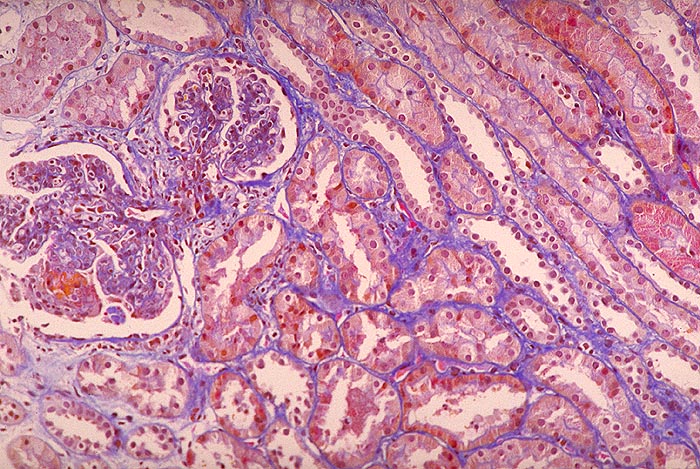

Endokapilläre Glomerulonephritis: Schlingennekrose

Glomeruläre Hyperzellularität infolge Vermehrung von neutrophilen Granulozyten und Monozyten. Frische Schlingennekrose mit Austritt von Fibrin in den Kapselraum bedeckt von einem ganz frischen Halbmond. Keine relevante Entzündung im umliegenden Interstitium.

Initial Glomerula vergrössert, blutarm, Schlingen ausgefüllt von gelapptkernigen Leukozyten und Monozyten. Später Mesangiumverbreiterung infolge Zellvermehrung (Mesangiumzellen und Monozyten). Keine mesangiale Matrixvermehrung. Glomerulumschlingen zum Teil wieder bluthaltig, teils von Monozyten angefüllt. Selten grosse, irregulär verteilte, subepitheliale Depots erkennbar.